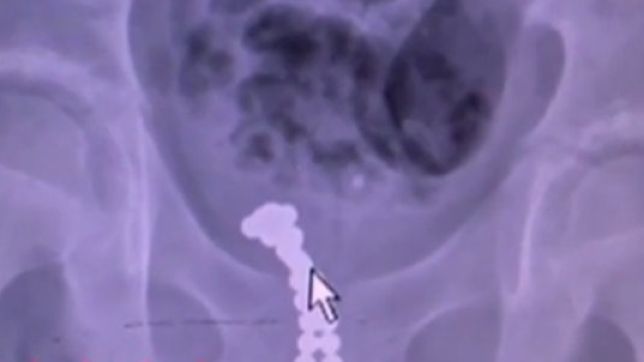

“As bolinhas estavam alinhadas em duas colunas e ficaram presas na área da uretra posterior”, afirmou em entrevista ao jornal chinês Kankanews o cirurgião responsável pela cirurgia, Dr.

Wang Yongbiao. Para conseguir fazer o procedimento sem maiores complicações, o médico utilizou outro imã para arrastar as bolinhas até a bexiga do garoto. Depois disso, ele realizou cirurgia de duas horas, chamada de cistostomia, que consiste na abertura da bexiga para retirada de obstruções do trato urinário.

A demora na cirurgia foi consequência do procedimento meticuloso para tirar uma bolinha de cada vez. O profissional afirmou que casos assim são raros, mas já aconteceram antes, principalmente com crianças. “Elas podem engolir facilmente esse brinquedo, ou inserir no corpo. Já fiz dois procedimentos semelhantes a esse”, afirmou.